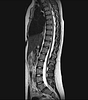

L’ imagerie ostéo articulaire est la spécialité de la radiologie consacrée à l’étude des os, articulations et muscles. Elle étudie l’ensemble de l’appareil locomoteur.

Dans cette spécialité toute les techniques d’imagerie vont être utilisées : la radiographie standard, l’échographie, le scanner et l’IRM.

• Les pathologies rachidiennes : discopathie, hernie discale, tassements

Dans certains cas en fonction de votre pathologie, le radiologue pourra vous proposer la réalisation d’examen complémentaires afin de préciser son diagnostic. Par exemple la réalisation d’une IRM dans les suites d’un examen radiographique ou échographique.